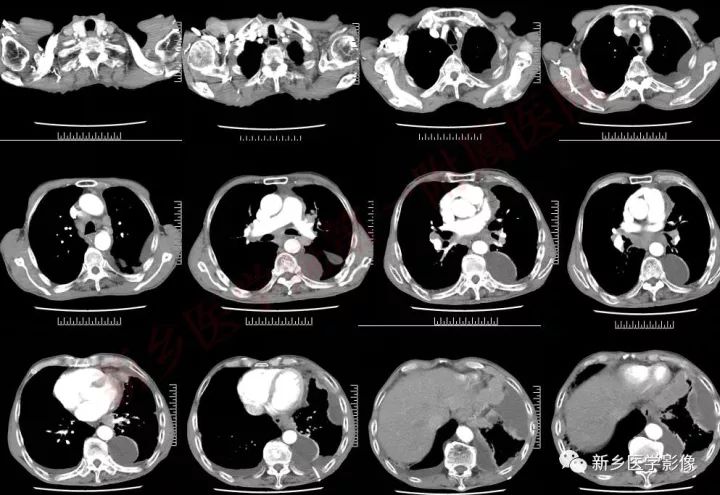

肿块形态及强化:

中央型小细胞肺癌主要起源于5级以上支气管,分叶少,边界较光滑,不易发生空洞,肿块一般沿支气管长轴蔓延,包绕支气管,增强后呈中度强化;周围型小细胞肺癌,肿块多呈结节状或葡萄状,结节状病灶多为单结节型,形态较规整,边缘较光滑,无分叶或浅分叶,毛刺征及胸膜凹陷出现率低;葡萄状病灶表现为沿小支气管生长的串珠状大小不等结节病灶,密度较均匀,少有空泡征、空气支气管征,增强后,出现轻中度强化。这主要与小细胞肺癌的病理形态有关,小细胞肺癌,癌细胞小而呈短梭形,胞浆少,癌细胞排列密集,因此形成的肿块密度较大,瘤体密实,内聚力强,纤维成分少,血供相对丰富,肿块各方向生长的速度也较均衡,使得小细胞肺癌肿块不容易形成较深的分叶和空洞。

血管:

小细胞肺癌的沿支气管壁生长的特点,加上其肿块周围的淋巴结、淋巴管弥漫受侵的特性,使得小细胞肺癌周围肺间质广泛受侵,间质增厚,其中的血管壁受侵甚至管腔内受侵有癌栓形成,造成受侵血管呈“冰冻状”。中央型小细胞肺癌,肿块较大时肿块与肺门、纵膈的肿大淋巴结融合,包绕临近较大血管形成“冰冻纵膈”。CT表现为肺动脉主干或分支最常见。

胸腔积液与胸膜

小细胞肺癌沿淋巴管扩散的特点,容易造成小叶间隔线增厚、凸起,当侵及胸膜时,可引起胸膜多发结节影或磨玻璃影,伴有恶性胸腔积液。CT表现为胸膜面不规则增厚、凹凸不整的细小结节影及胸腔积液,增强可见增厚的胸膜及结节影轻至中度强化表现。按照美国退伍军人医院肺癌研究组分期系统标准,双侧胸腔积液发生时,病情已进展到广泛期,对于患者的治疗和预后将产生重要的影响

小细胞肺癌转移特点:

小细胞肺癌早期即发生转移,常见胸外转移发生率依次为脑、肝、肾上腺、后腹膜淋巴结及骨转移等。与非小细胞肺癌的转移顺序脑、肾上腺和骨骼比较,小细胞肺癌的肝、后腹膜淋巴结等的转移,往往会疏忽和遗漏,因此阅片时若怀疑小细胞肺癌,一定要注意观察肝、后腹膜、肾上腺等器官组织。同样若观察到上述器官组织有转移征象时,亦可以反证肺部肿块的小细胞肺癌的性质。